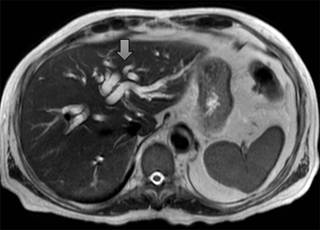

La secuencia de colangiorresonancia magnética puede delimitar el sitio de obstrucción definiendo si la vía biliar intrahepática y extrahepática está afectada, así como determinar si el compromiso el mecanismo de la obstrucción en intraluminal o extraluminal (Figuras 3 y 4).

Figura 3: Corte axial potenciado en T2. Se observa dilatación de la vía biliar intrahepática (flecha), la cual tiene un aspecto tortuoso, sin observar lesiones en su interior.